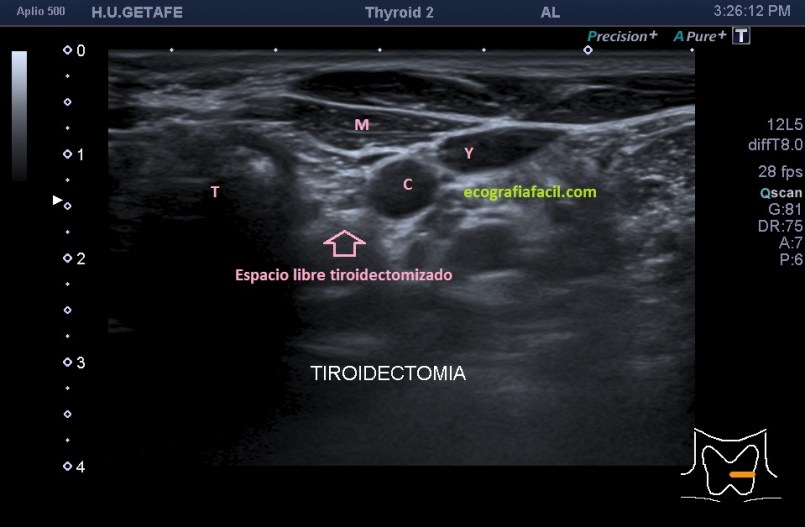

cuando hacemos un tiroidectomizado, vemos esto:

Quiero que veas las dos imágenes y compares.

Lo más importante, saber cómo es la «normalidad» de una región tiroidectomizada, te la dejo en las dos siguientes imágenes, veremos una zona hiperecogénica correspondiente a la grasa que ocupa el espacio que ya no ocupa el tiroides. Cuando el paciente es diagnosticado de ca de tiroides suele realizarse tiroidectomía total.